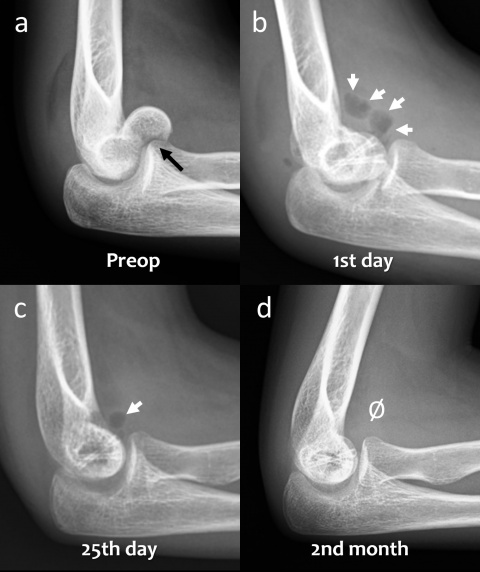

1. Einleitung

Magnesium-Kompressionsschrauben. (a) Mediale Spunggelenksfraktur

(b) Kahnbeinfraktur (c) Radiuskopffraktur (d) Distale Radiusfraktur (e)

Laterale Spunggelenksfraktur (f) Fingerfraktur (g) Tillaux-Fraktur im

Jugendalter (h) Abriss des hinteren Kreuzbands (ı) Capitulum-humeri-

Fraktur

(schwarzer Pfeil) in der präoperativen lateralen Röntgenaufnahme des

Ellenbogens. (b) Röntgenaufnahme des Ellenbogens mit Gasansammlung

im Weichgewebe (weiße Pfeile) am ersten postoperativen Tag. (c)

Röntgenaufnahme des Ellenbogens 25 Tage nach der Operation, die

Gasmenge hat sich verringert (weißer Pfeil). (d) Bei der radiographischen

Nachbeobachtung nach 2 Monaten ist kein Gas im Weichgewebe

mehr sichtbar.

In frühen postoperativen Röntgenaufnahmen lässt sich auch Gas im Weichgewebe beobachten, das sich in den Gewebeschichten verteilt. Klinisch produziert dieses Gas aber keine wahrnehmbare Krepitation unter der Haut oder ähnliche Symptome. Die Gasschatten im Weichgewebe bilden sich gewöhnlich rasch zurück (Abbildung 3). In frühen postoperativen Röntgenaufnahmen stellt Gas im Weichgewebe oft ein alarmierendes Signal dar, da es – bei herkömmlichen Metallimplantaten – mit gasbildenden anaeroben Infektionen in Verbindung gebracht wird. Die Bildung von Gas während der Degradation von Mg-Implantaten hat einen vollkommen anderen Hintergrund – es handelt sich weder um eine Lockerung des Implantates noch gar um eine Infektion. Während des Abbauprozesses via Korrosion nimmt die Gasmenge zu und breitet sich im trabekulären Knochenanteil aus. Schließlich wird es jedoch vollständig resorbiert und die Mg-Schrauben zeichnen sich zunehmend prominenter ab (Abbildung 4). Tierstudien haben gezeigt, dass die Schraube schließlich durch kortikales Knochengewebe ersetzt wird (7).